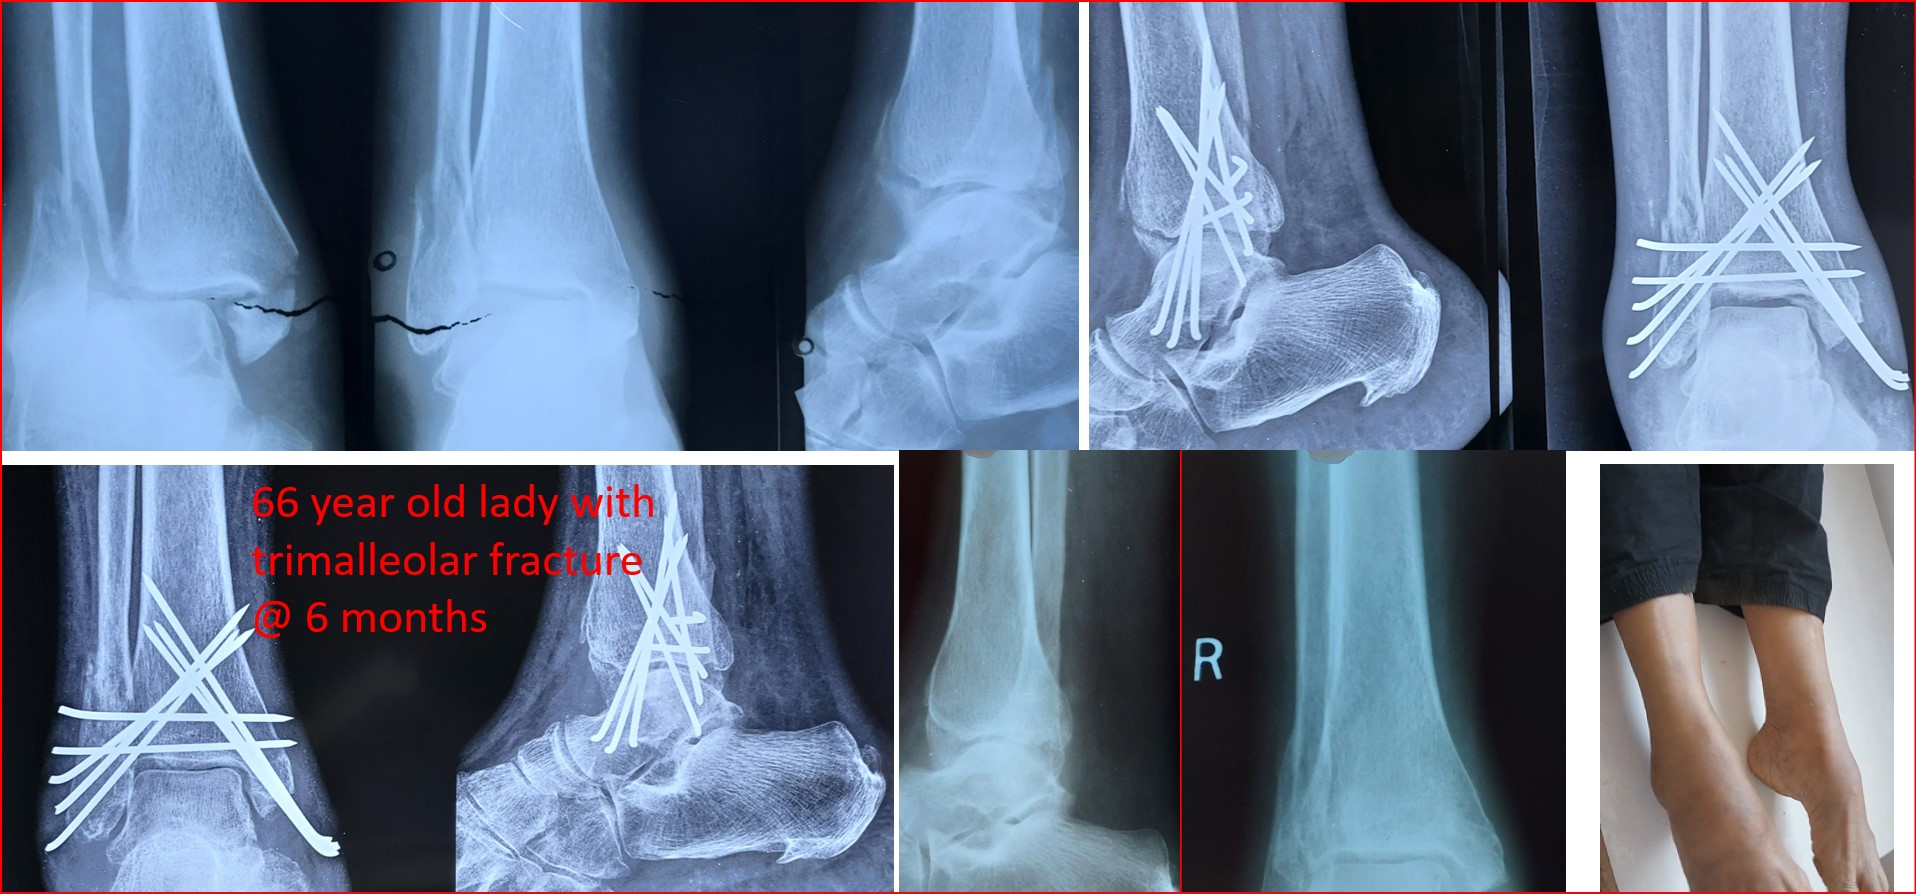

CRPP ( Closed Reduction Percutaneous Pinning )

• CRPP is a minimally invasive surgical procedure under regional anesthesia and the patient can be discharged on the 2nd postoperative day.

• No skin incision is required, and fracture heals faster than open surgeries as there is no iatrogenic soft tissue damage or disturbance to the fracture hematoma.

• No implants projecting outside the skin and hence painless adjacent joint movement is possible immediately after CRPP.

• It can be applied to any intraarticular fractures, distal end radius, elbow, ankle and foot.